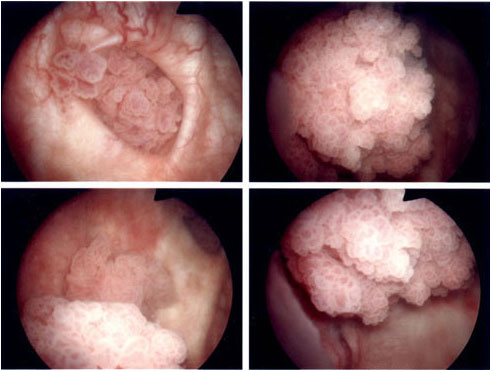

I VERI EFFETTI DEL FUMO, CANCRO ALLA BOCCA!

!!!VIDEO SHOCK!!!

Ecco la testimonianza di una ragazza affetta dal cancro alla bocca per colpa del fumo!

SMETTETE PRIMA DI RIDURVI IN QUESTO STATO, MEGLIO ANCORA, NON INIZIATE MAI!